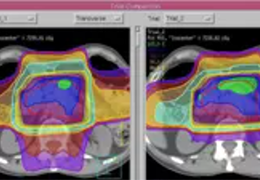

BrainVoyager performs a wide range of statistical analyses including; parametrical mapping, contribution maps, Independent Component Analysis (ICA), Region-of-interest analysis and Event-related fMRI analysis. specifications.

Parametric and non-parametric statistical maps may be superimposed both on the original functional scans as well as onto T1-weighted 2D or 3D anatomical reference scans. Time courses of selected regions-of-interest (ROIs) are available both in 2D and 3D representations. Statistical maps may be computed either in the 2D or 3D representation since structural as well as functional 4D data (space x time) are transformed into Talairach space. This allows you to compare activated brain regions across different experiments and across different subjects

Segmentation of tissue (e.g., isolating the brain, differentiating gray and white matter) is performed using region-growing methods, filter operations as well as the application of 3D templates. Using the mouse it is very easy to explore a 3D volume with superimposed pseudocolor-coded statistical maps in a four-window representation showing a sagittal, coronal, transversal and oblique section. Based on a (segmented) 3D data set a three-dimensional reconstruction of the subjects' head and brain can be calculated and displayed from any specified viewpoint using volume or surface rendering.